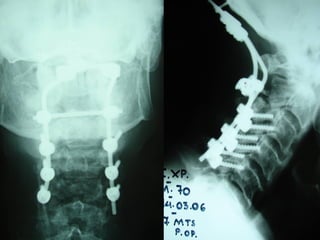

Operative treatmentOperative treatment

CervicalCervical

epiduralepidural

abscessabscess

Anterior decompressionAnterior decompression

±± stabilizationstabilization

Posterior decompressionPosterior decompression

PosteriorPosterior

decompressiondecompression

andand

stabilizationstabilization

Lumbar abscessLumbar abscess

and stabilizationand stabilization

44thth

casecase

Diak. Nick.

M 61

possible origin

superficial skin infection at the elbow area

Symptoms

 High fever

 Back Pain

Laboratory

 E.S.R. 

 Leucocitosis 

 Neutro 

Posterior procedurePosterior procedure

Culture

Staph. aureous

Anterior procedureAnterior procedure

Follow upFollow up

Antibiotic treatment

Various schemes

 I.V. – Oral

for 6 months

Sufficient recovery